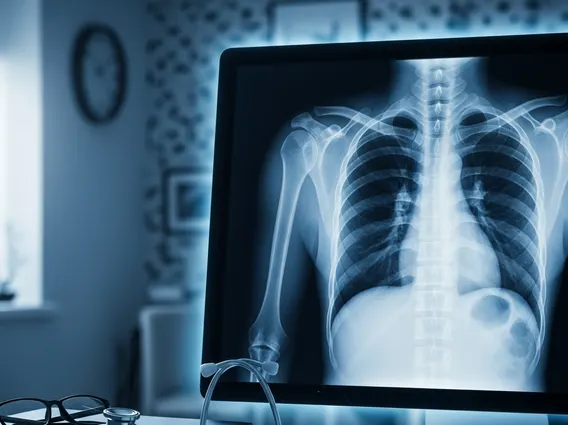

Interpreting Chest X-Ray Results

The process of interpreting chest x-ray results is performed by a radiologist, a medical doctor specializing in interpreting medical images. The radiologist examines the images for any abnormalities in the size, shape, and position of the heart, lungs, and other structures. They look for signs of infection, inflammation, fluid accumulation, tumors, fractures, or other indicators of disease. For example, pneumonia might appear as white patches (infiltrates) in the lungs, while an enlarged heart could suggest heart failure.

Once the radiologist has analyzed the images, they will provide a detailed report to the referring physician. The physician then discusses these findings with the patient, explaining what the results mean in the context of their symptoms and medical history. Further tests may be recommended based on the findings to confirm a diagnosis or guide treatment. It’s important to remember that a chest X-ray is one piece of the diagnostic puzzle, and its results are always considered alongside other clinical information.